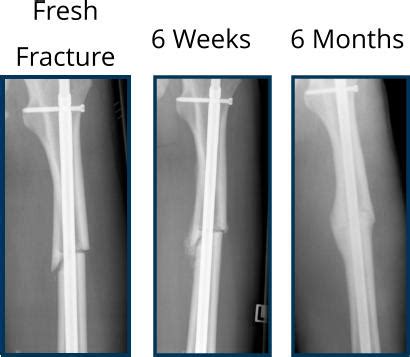

Source: infortekhr.pages.dev How Long Does A Tibia Fracture Take To Heal Tibia fractures — tibia shaft fractures also have , While it can provide temporary relief, the formation of fibrocartilage, which is less resilient than hyaline cartilage, might lead to the necessity for additional interventions in the future (Mohan et al., 2015). How Long Does a Microfracture Take to Heal The healing time for a microfracture largely depends on various factors, including the individual's health, age, and the location of.

How Long Does A Tibia Fracture Take To Heal Tibia fractures — tibia shaft fractures also have . Though the clot often does form, it has a varying ability to form into adequate cartilage repair material. The number of microfractures created depends on the size of the joint being treated